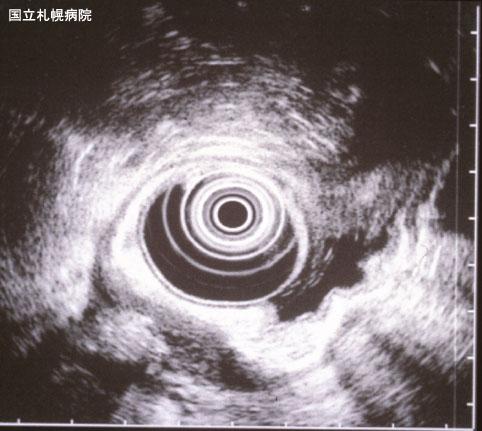

症例提示(所在地,施設名等): 北海道・ 北海道がんセンター

疾患(病理主体)の分類炎症性・潰瘍性疾患/その他

部位(臓器別)胃(部位)/体部

検査方法エコー

病変の最大径(ミリ)40以上